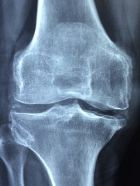

무릎 퇴행성관절염 증상 원인 관리방법 등 무릎 퇴행성관절염 정보에 대해 알아보도록 하겠습니다. 무릎 퇴행성 관절염은 무릎에 생기는 퇴행성 관절염을 의미합니다. 퇴행성 관절염은 관절을 보호하는 연골이 점차 손상되고 염증이 생기면서 통증이 발생하는 만성 질환입니다. 무릎 퇴행성 관절염은 나이가 들면서 생기는 경우가 많지만, 비만, 과도한 운동, 외상 등에 의해서도 발생할 수 있습니다. 무릎 통증이 심해지면 일상생활에 불편을 겪고, 심한 경우에는 수술적 치료를 받아야 할 수도 있습니다. 따라서 무릎 퇴행성 관절염을 예방하고 관리하는 것이 중요합니다.

무릎 퇴행성 관절염 증상

무릎 퇴행성 관절염의 증상은 다음과 같습니다.

- 무릎 부위의 통증: 초기에는 무릎을 움직일 때 심해지고, 병이 진행되면 휴식 상태에서도 지속됩니다. 오래 걷거나 뛰거나 계단을 오르내릴 때 통증이 심해집니다.

- 무릎 부위의 부종: 관절에 염증이 생기면 무릎이 붓고 따끔하게 느껴집니다. 부종이 심해지면 무릎의 모양이 변할 수 있습니다.

- 무릎 부위의 강직: 관절 운동 범위가 감소하면서 무릎을 구부리거나 펴는 것이 어려워집니다. 쪼그리고 앉거나 일어서는 것이 힘들어집니다.

- 무릎 부위 마찰음: 연골이 닳아서 관절면이 불규칙해지면 무릎을 움직일 때 삐걱거리는 소리가 날 수 있습니다. 이것은 골극이라고 하는 골조직의 비정상적인 성장 때문입니다.

- 무릎 부위의 변형: 병이 심하게 진행되면 무릎의 모양이 바뀔 수 있습니다. O자형 다리나 X자형 다리로 변할 수 있으며, 이는 보행에도 영향을 줍니다.